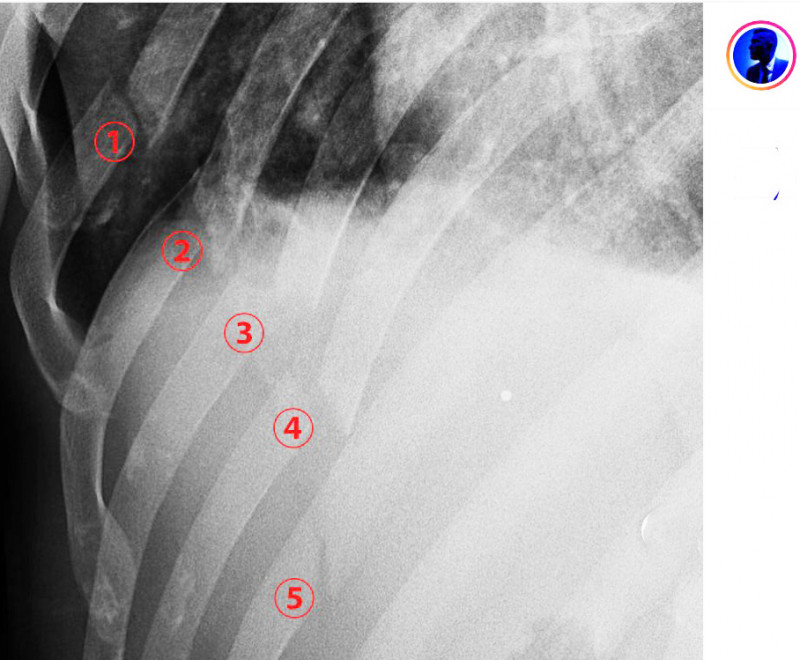

拡大レントゲン写真、肋骨5箇所が折れている@blackeagle_170より